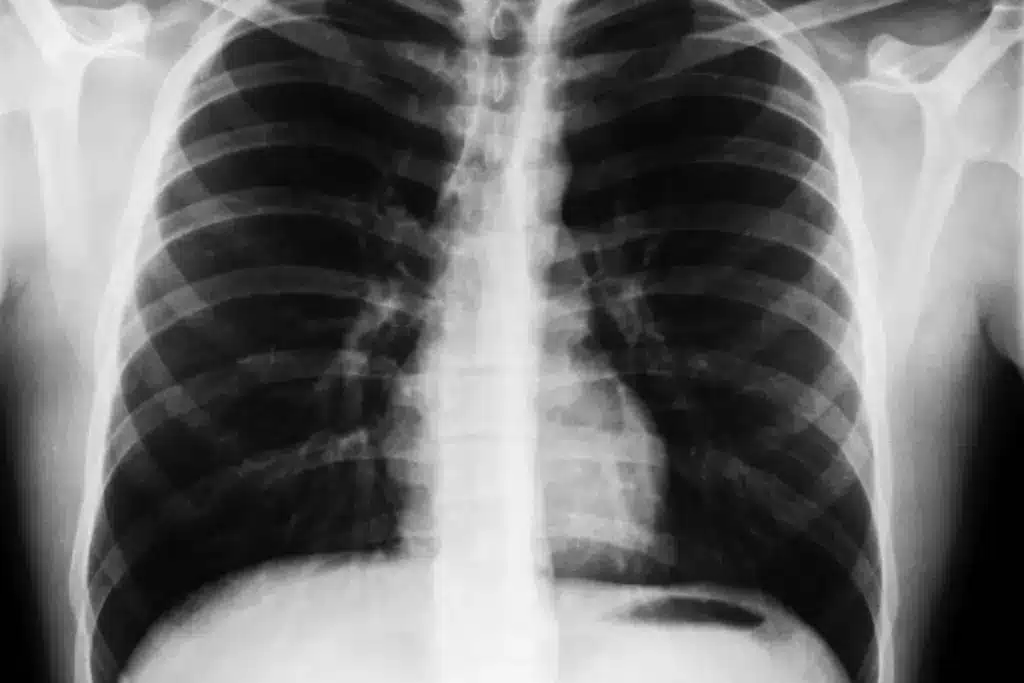

Chest X-rays are used to start checking for breathing problems. But they can’t directly say if someone has asthma. We’ll look at why: because most asthma patients have normal X-rays and X-rays aren’t the first choice for diagnosing asthma.

Research shows that up to 75% of asthma patients have normal chest X-rays. This is because asthma mainly affects the small airways. These changes are not seen on a standard X-ray. So, a normal X-ray doesn’t mean you don’t have asthma.

Many asthma patients have normal chest X-rays. But, some show signs like hyperinflation or bronchial wall thickening. These signs show how severe asthma is and help choose treatments.